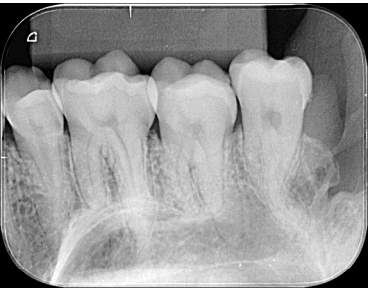

Para correta montagem de radiografias odontológicas, é necessário saber pontos anatômicos que identifiquem a posição do filme e os elementos dentários em questão.

Diante disso, analise a radiografia ilustrada e assinale a alternativa correta.